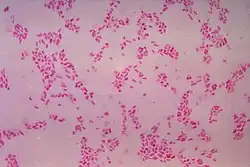

For partially impacted teeth in those over 20 year of age, the most common pathology seen, and the most common reason for wisdom teeth removal, is pericoronitis or infection of the gum tissue over the impacted tooth. The bacteria associated with infections include Peptostreptococcus, Fusobacterium, and Bacteroides bacteria. The next most common pathology seen is cavities or tooth decay. Fifteen percent of people with retained wisdom teeth exposed to the mouth have cavities on the wisdom tooth or adjacent second molar due to a wisdom tooth. The rate of cavities on the back of the second molar has been reported anywhere from 1% to 19% with the wide variation attributed to increased age.[12]